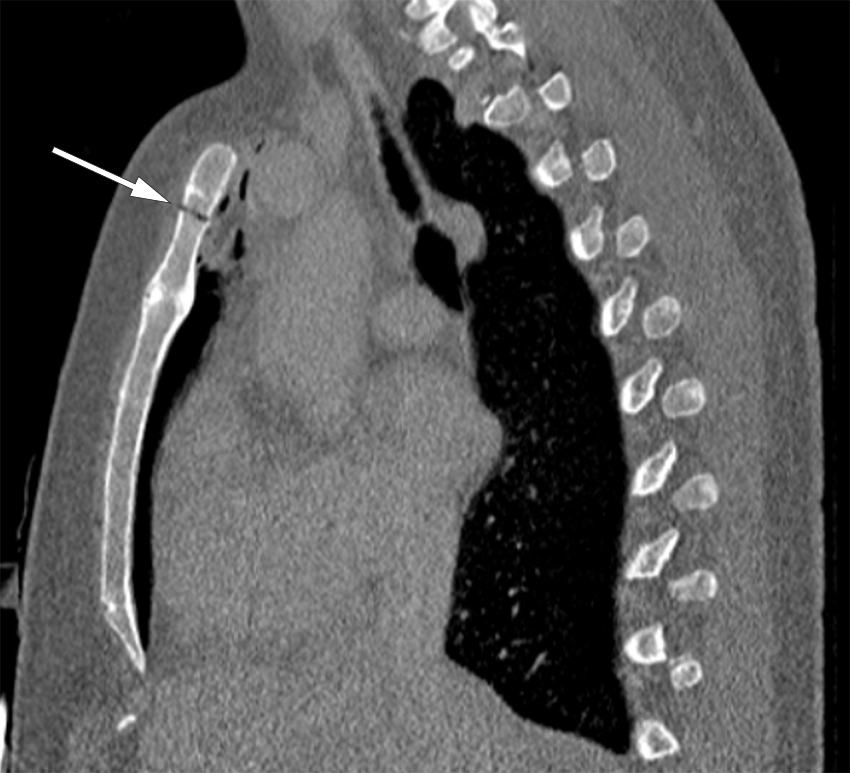

CT-bildet viser stikk-kanal gjennom manubrium sterni (bilde 1: sagittalt, benvindu) og retrosternal luft (bilde 2 på tidsskriftet.no: aksialt, lungevindu) etter aspirasjon av benmarg fra sternum hos en ung kvinne med akutt myelogen leukemi. Benmargsundersøkelsen ble utført standardmessig med sternalnål med skjold på korrekt sted, sentralt i manubrium sterni. Etter at mandrengen ble fjernet, hørtes en surklelyd idet pasienten trakk pusten. Det var ingen motstand ved forsøk på aspirasjon, benmarg lot seg ikke aspirere og pasienten fikk samtidig lett ubehag i venstre skulder. Hun hadde ingen andre symptomer.

CT thorax ble tatt umiddelbart og påviste perforasjon gjennom bakre sternumkorteks og luft retrosternalt. CT-undersøkelsen viste ingen tegn til punksjon av lunge eller pneumotoraks, og man antar derfor at luften ble sugd inn gjennom nålen idet pasienten trakk pusten. Pasienten hadde ingen andre symptomer, og vitalia var stabile. Hun ble derfor behandlet konservativt med sengeleie og oksygen og kunne skrives ut etter 24 timer. Det var ingen ytterligere komplikasjoner, og videre behandlingsforløp for leukemi ble ikke påvirket. I forbindelse med behandlingsforløpet er det tatt gjentatte røntgen toraks, med normale funn.

Som CT-bildene viser, har manubrium sterni en tykkelse på ca. 1 cm. Sternalnål med skjold skal derfor alltid benyttes, og andre deler av sternum enn manubrium sterni skal ikke punkteres. Undersøkelsen kan gjøres også under antikoagulasjonsbehandling og ved alvorlig trombocytopeni (trombocytter under 10 ∙ 109/L) uten transfusjon av trombocyttkonsentrat. Ved mistanke om benmargssykdom foreligger det ingen kontraindikasjoner mot undersøkelsen.